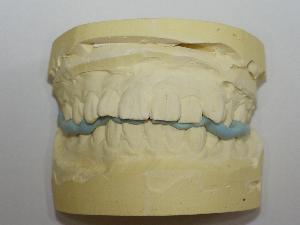

治療前模型       治療後予測模型

現在の歯の状況を把握するために、レントゲンや、顔・口の中の写真、歯の型をとります。